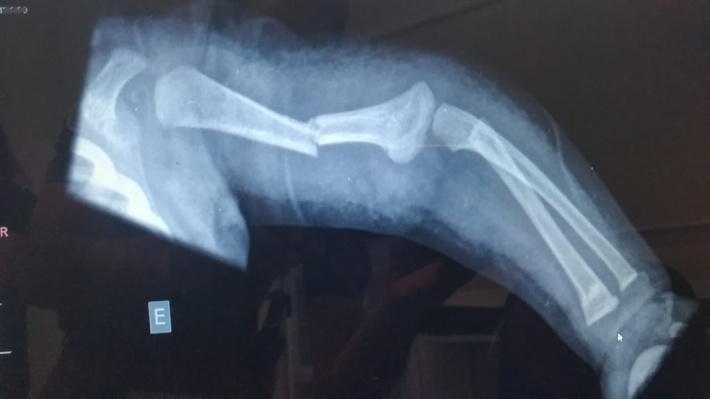

Raio-X mostra braço de bebê de três meses com fraturas — Foto: Arquivo pessoal

Segundo a PM, a equipe foi acionada por volta das 14h15 pela unidade onde a criança deu entrada com os pais, com fratura em duas partes de um dos braços.